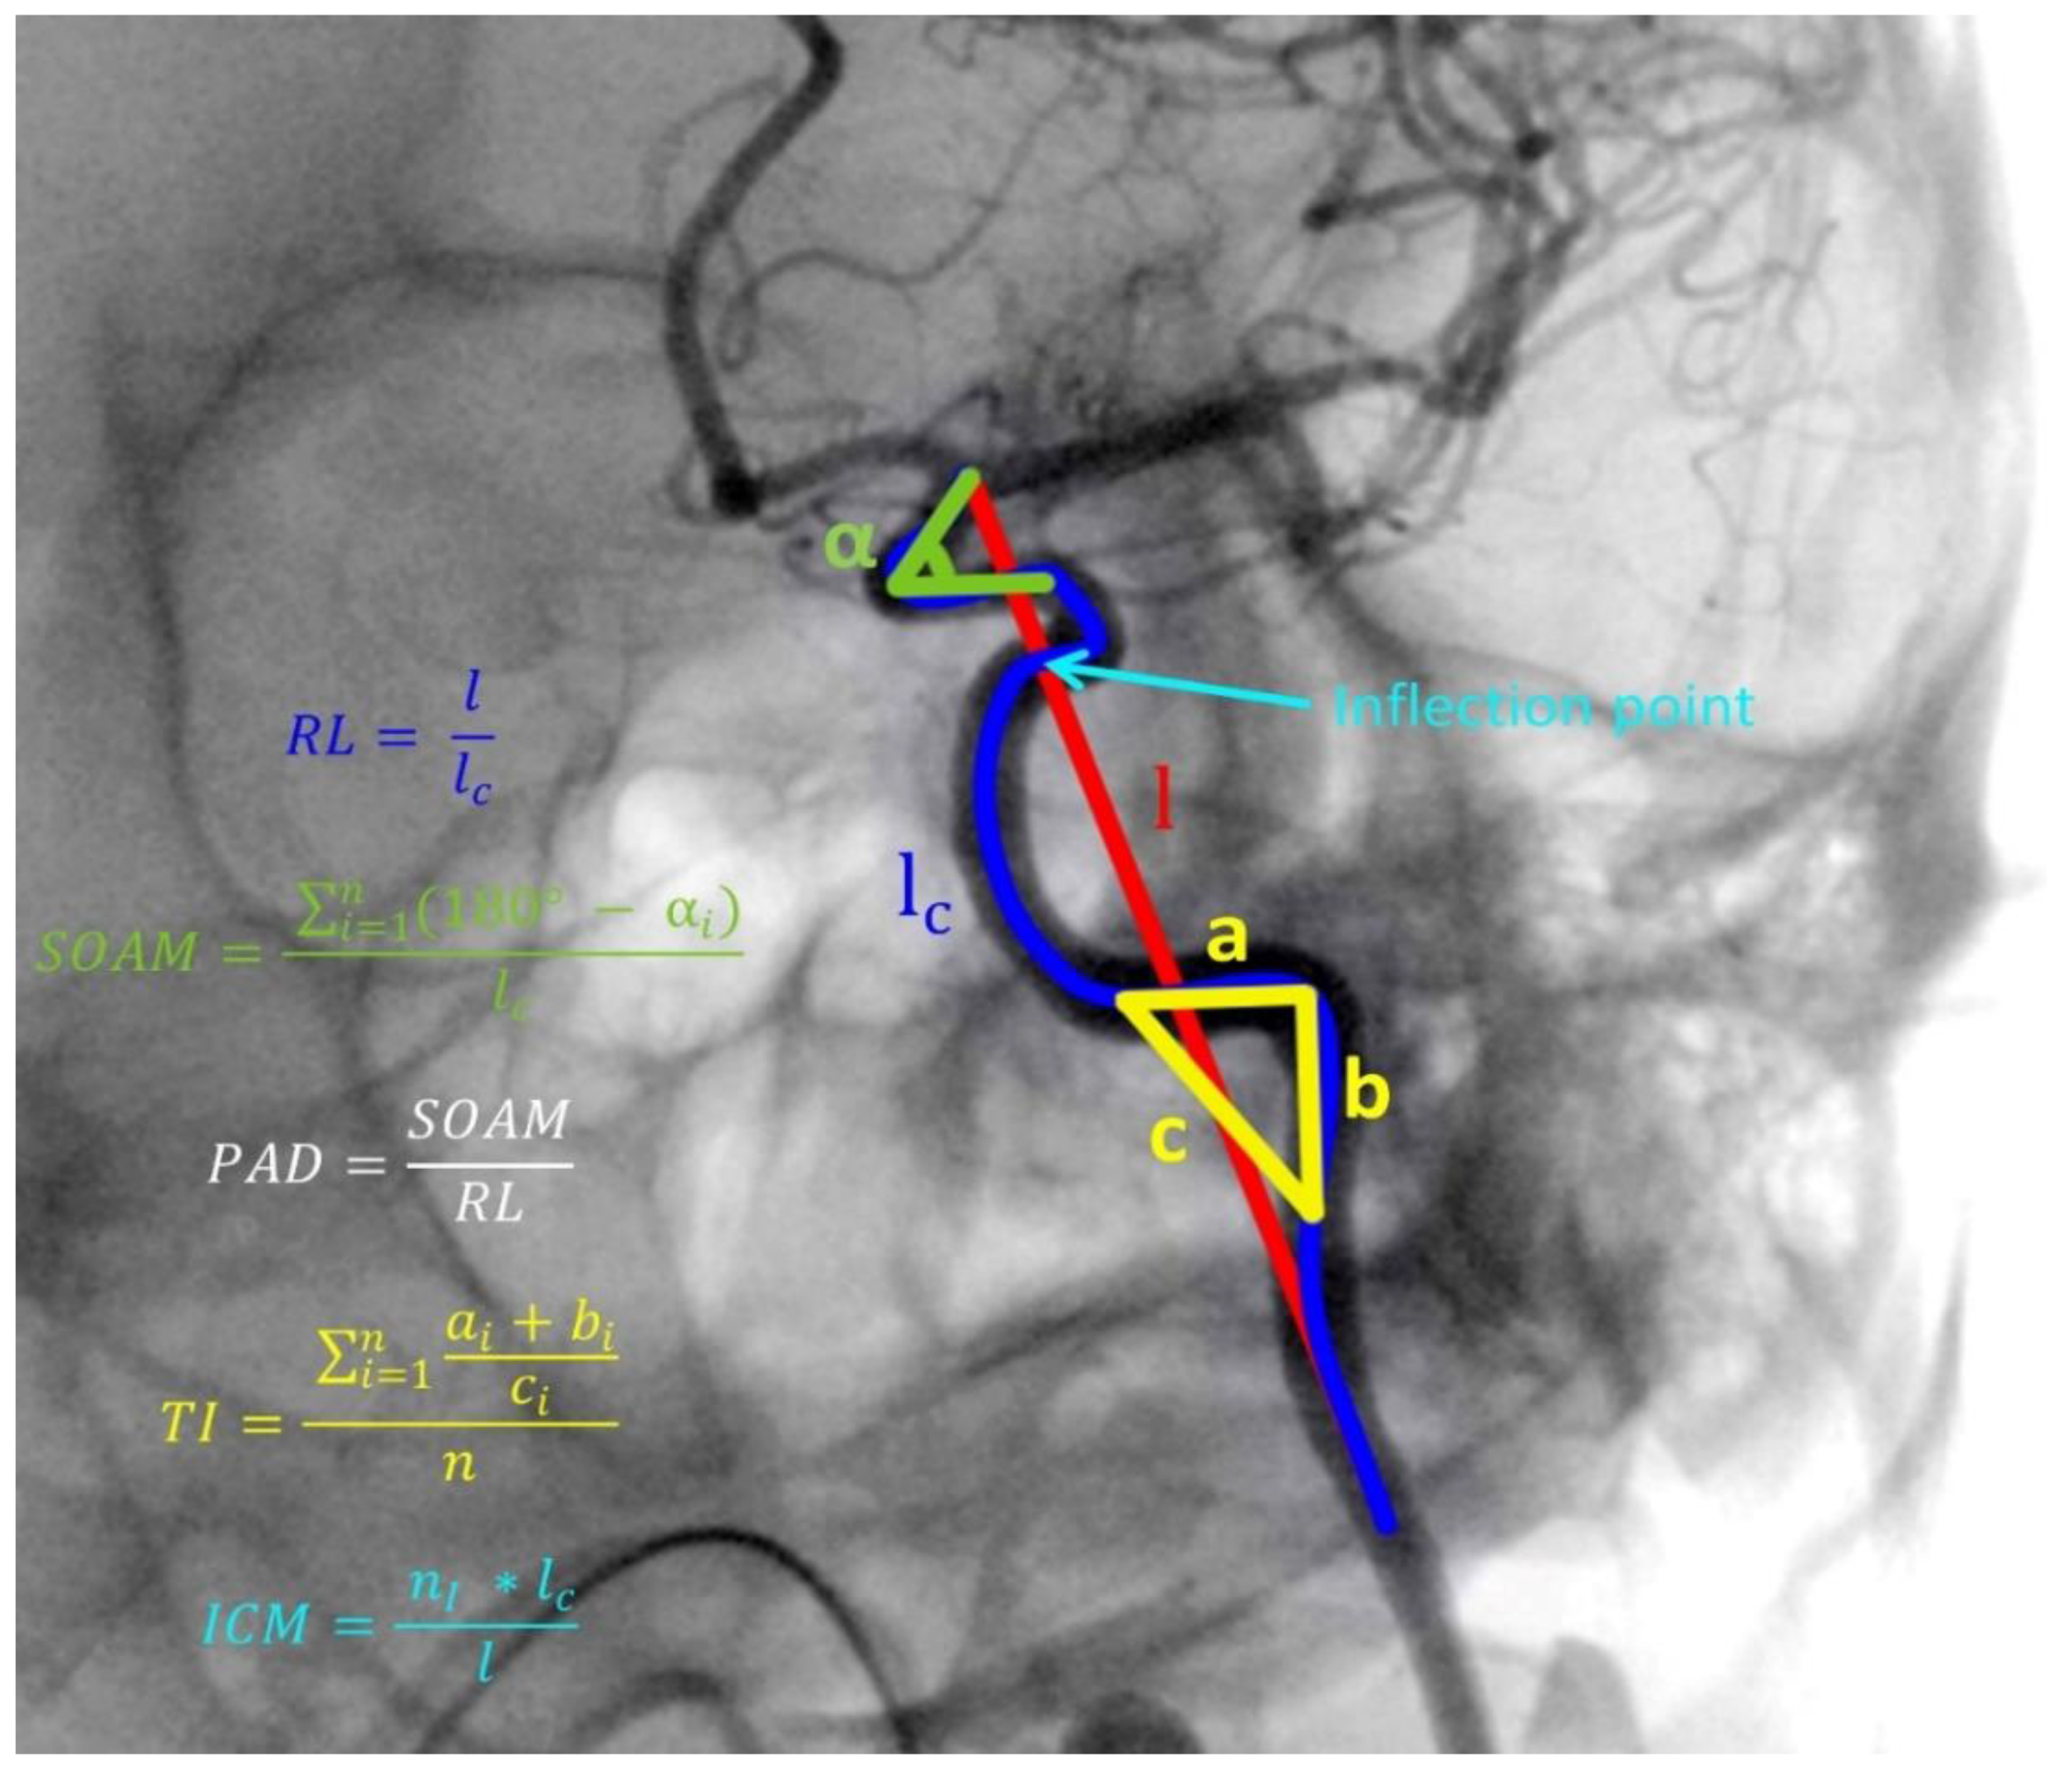

| Tortuosity Descriptors | |||

| Relative Length ± SD | 0.46 ± 0.19 | 0.51 ± 0.17 | 0.023 |

| Sum of Angle Metrics ± SD | 0.39 ± 0.21 | 0.32 ± 0.21 | 0.003 |

| Product of Angle Distance ± SD | 0.38 ± 0.19 | 0.32 ± 0.21 | 0.011 |

| Triangular Index ± SD | 0.30 ± 0.11 | 0.27 ± 0.14 | 0.034 |

| Inflection Count Metric ± SD | 0.30 ± 0.16 | 0.22 ± 0.12 | <0.001 |